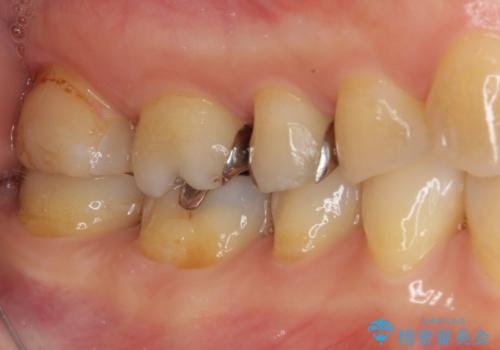

- 奥歯の銀歯をすべてゴールドにすることを希望された患者様です。

セラミックインレーによる補綴治療も提案しましたが、ご自身で強い咬合力を認識しており、歯にもインレーにもダメージの少ないゴールドインレーにて処置することとしました。